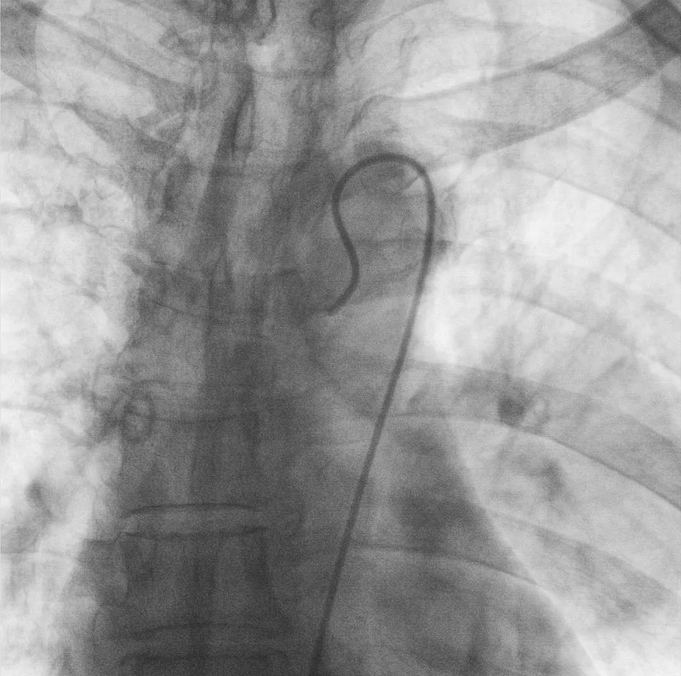

在普愛醫療移動式平板介入中C影像的引導下,醫生為患者實施雙側支氣管動脈栓塞+化療灌注術。

在微導絲的配合下,先后分別超選擇①至3支左側支氣管動脈腫瘤供血動脈,經微導管推注栓塞微粒球栓塞腫瘤動脈。栓塞結束后,再次用移動式平板介入中C做造影檢查,見腫瘤染色消失。